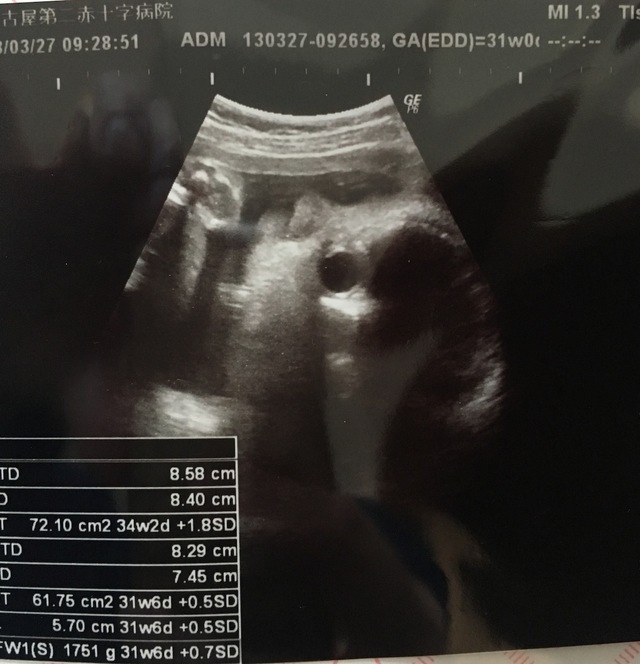

31週0日(31w0d・男の子)|まめんこ さん(32歳)

エコー写真撮影時のエピソード:

子宮に顔を押し付けて鼻ぺちゃです。3人目の妊娠ですが、何度見てもエコー写真はワクワクします。しかし、今回の子はなかなかいい顔を見せてくれなくて、どんな顔をしているのかとても楽しみです。妹が欲しいと言っていたお姉ちゃんも楽しみにしてくれています。